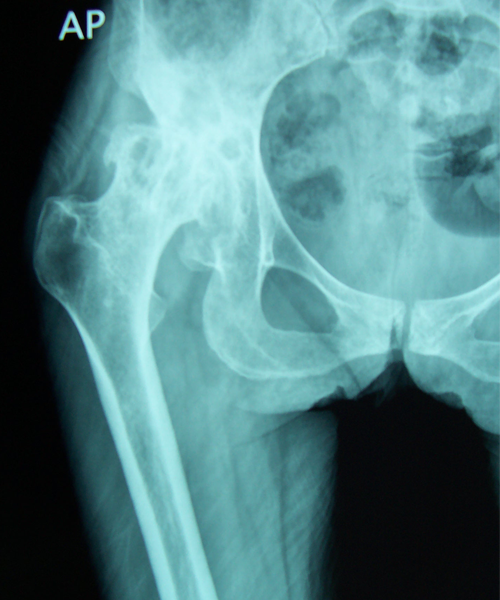

Case:4 Post Tuberculous Ankylosed Hip

Arthroscopy Surgeon in Ahmedabad|Best Trauma Surgeon in Ahmedbad

Pre-op

Arthroscopy Surgeon in Ahmedabad|Orthopedic Oncology Doctor

Post-op